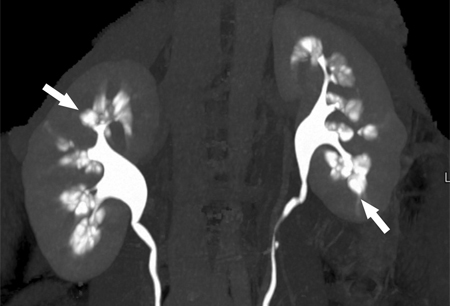

Rim em esponja medular

Urografia por tomografia computadorizada (TC) mostrando realce papilar com cálculos nos túbulos coletores dilatados (setas)

De Maw AM, et al. Am J Kidney Dis. julho de 2007;50(1):146-50, usado com permissão